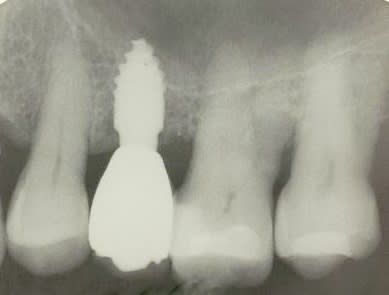

> Voici le cas en image

> Mon doute portait donc sur la face vestibulaire de l'implant en place de 43.

>

> Implant4.5*11 Astra

> Excusez moi pour la pano avec le stellite.

Serrage manuel, sans lambeau. Extraction implantation immédiate

le 4.5*11 me semblait convenable. J'avais peur que si je metais du 4*11 l'espace entre les cretes vestibulaires et l'implant allait creer une recession si je ne comblait pas ce vide

Rappelons qu'en mesurant j'ai 1.25 mm d'os au final et pas 0.5-0.8mm